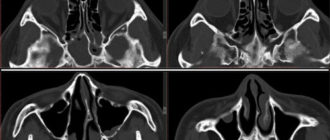

Сфеноидит – симптомы и лечение, фото, антибиотики Из этой статьи Вы узнаете: что такое